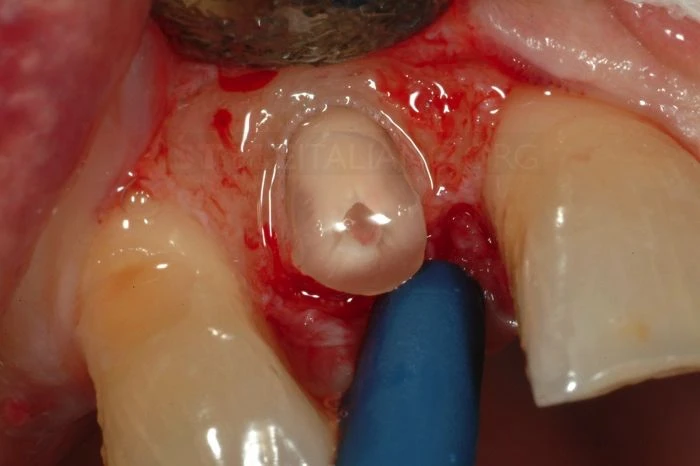

Sau khi lật vạt, thực hiện phẫu thuật tạo hình xương phía ngoài nhưng phải để chân răng có chiều cao tối thiểu 2mm so với mào xương ổ răng. 2mm này rất quan trọng để tạo khoảng trống đủ cho bám dính sinh học.

Đây là thời điểm để đặt tấm cao su cách ly.

Trước khi gắn răng vào đúng vị trí cần phải điều trị để giảm số lượng vi khuẩn đặc biệt trong trường hợp này vì vị trí gắn sẽ được phủ bởi vạt: kết quả là răng đã được cách ly, không cần khâu dưới vạt, với tấm cao su cách ly đã được rửa sạch bằng 0,2% Chlorexidine (Curaden – Curasept 0,20% + Ialuronic Acid).

Sau khi đặt tấm cao su cách ly với kẹp, tiến hành điều trị tủy và tạo khoảng đặt chốt.